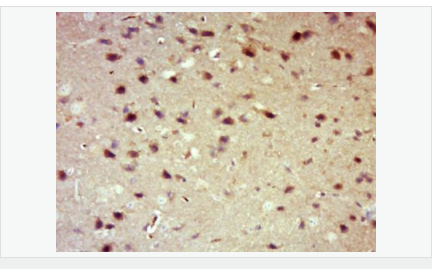

| 產(chǎn)品應(yīng)用 | WB=1:500-2000 IHC-P=1:100-500 IHC-F=1:100-500 Flow-Cyt=1μg /test. IF=1:100-500 (石蠟切片需做抗原修復(fù)) not yet tested in other applications. optimal dilutions/concentrations should be determined by the end user. |

| 產(chǎn)品介紹 | 14-3-3 are activates tyrosine and tryptophan hydroxylases in the presence of Ca (2+)/calmodulin-dependent protein kinase II, and strongly activates protein kinase C. Is probably a multifunctional regulator of the cell signaling processes mediated by both kinases. Activates the ADP-ribosyltransferase (exoS) activity of bacterial origin. 14-3-3 proteins are localized in neurons, and are axonally transported to the nerve terminals. They may be also present, at lower levels, in various other eukaryotic tissues. It belongs to the 14-3-3 family. This antibody is reactive with 14-3-3 Alpha, Beta, Gamma, Delta, Epsilon. Function: Adapter protein implicated in the regulation of a large spectrum of both general and specialized signaling pathways. Binds to a large number of partners, usually by recognition of a phosphoserine or phosphothreonine motif. Binding generally results in the modulation of the activity of the binding partner. Subunit: Interacts with CDK16 and BSPRY. Interacts with WEE1 (C-terminal). Interacts with SAMSN1. Interacts with MLF1 (phosphorylated form); the interaction retains it in the cytoplasm. Interacts with Thr-phosphorylated ITGB2. Interacts with BCL2L11. Homodimer. Heterodimerizes with YWHAE. Homo- and hetero-dimerization is inhibited by phosphorylation on Ser-58. Interacts with FOXO4, NOXA1, SSH1 and ARHGEF2. Interacts with Pseudomonas aeruginosa exoS (unphosphorylated form). Interacts with BAX; the interaction occurs in the cytoplasm. Under stress conditions, MAPK8-mediated phosphorylation releases BAX to mitochondria. Interacts with phosphorylated RAF1; the interaction is inhibited when YWHAZ is phosphorylated on Thr-232. Interacts with TP53; the interaction enhances p53 transcriptional activity. The Ser-58 phosphorylated form inhibits this interaction and p53 transcriptional activity. Interacts with ABL1 (phosphorylated form); the interaction retains ABL1 in the cytoplasm. Interacts with PKA-phosphorylated AANAT; the interaction modulates AANAT enzymatic activity by increasing affinity for arylalkylamines and acetyl-CoA and protecting the enzyme from dephosphorylation and proteasomal degradation. It may also prevent thiol-dependent inactivation. Interacts with AKT1; the interaction phosphorylates YWHAZ and modulates dimerization. Interacts with GAB2 and TLK2. Subcellular Location: Cytoplasm. Melanosome. Note=Located to stage I to stage IV melanosomes. Post-translational modifications: The delta, brain-specific form differs from the zeta form in being phosphorylated. Phosphorylation on Ser-184 by MAPK8; promotes dissociation of BAX and translocation of BAX to mitochondria. Phosphorylation on Ser-58 by PKA; disrupts homodimerization and heterodimerization with YHAE and TP53. This phosphorylation appears to be activated by sphingosine. Phosphorylation on Thr-232; inhibits binding of RAF1. Similarity: Belongs to the 14-3-3 family. SWISS: P31946 Gene ID: 7529 Database links: Entrez Gene: 7529 Human Entrez Gene: 54401 Mouse Omim: 601289 Human SwissProt: P31946 Human SwissProt: Q9CQV8 Mouse Unigene: 643544 Human Unigene: 34319 Mouse Unigene: 485025 Mouse Unigene: 8653 Rat Important Note: This product as supplied is intended for research use only, not for use in human, therapeutic or diagnostic applications. 信號傳導(dǎo)(Signaling Intermediates) 14-3-3蛋白是一個涉及調(diào)節(jié)細胞凋亡、促細胞分裂信號傳導(dǎo)和細胞周期關(guān)卡的蛋白質(zhì)家族。它被認為是通過與絲氨酸殘基磷酸化的蛋白質(zhì)的結(jié)合介導(dǎo)的信號傳導(dǎo)中的關(guān)鍵調(diào)節(jié)物。通過與Bad(相關(guān)死亡因子)的結(jié)合, 14-3-3 蛋白由于將Bad隔離于胞液而防止了細胞凋亡。 蛋白是14-3-3家族成員。它廣泛分布于哺乳動物、兩棲類、昆蟲、植物和酵母菌的真核生物高度保守性多功能蛋白質(zhì)。 目前已知至少有16個成員。此抗體識別分子量為30-31kDa的14-3-3蛋白αβγδε亞型。 |